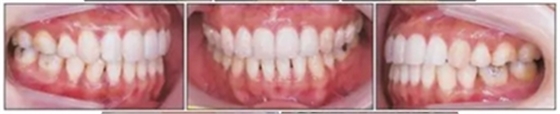

治療后面部和口內(nèi)照片顯示治療結(jié)果很成功(Figure 8)?;颊叩拿嫘瞳@得了非常顯著的改善,尤其是在唇部區(qū)域。覆合從-3.5mm增大到3.5mm,覆蓋從1.2mm增大到2.0mm。獲得了I類磨牙關(guān)系,沒有擁擠(Figures8 and 9)。